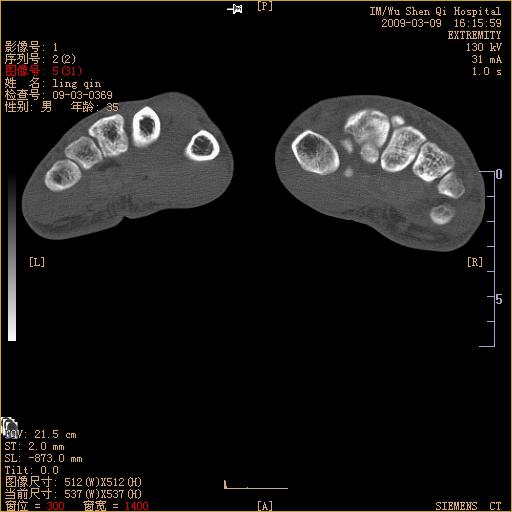

标题: CT18570:右手外伤10余天 [打印本页]

标题: CT18570:右手外伤10余天

请上传x线平片。舟状骨骨折可能大。

腕部有骨折、脱位,骨科面对ct片如何采取措施?三维一下。

请上传x线平片,腕骨多骨骨折

舟状骨骨折。

左侧舟骨及桡骨茎突骨折,第一掌骨基底部好像也有骨折,建议上传平片